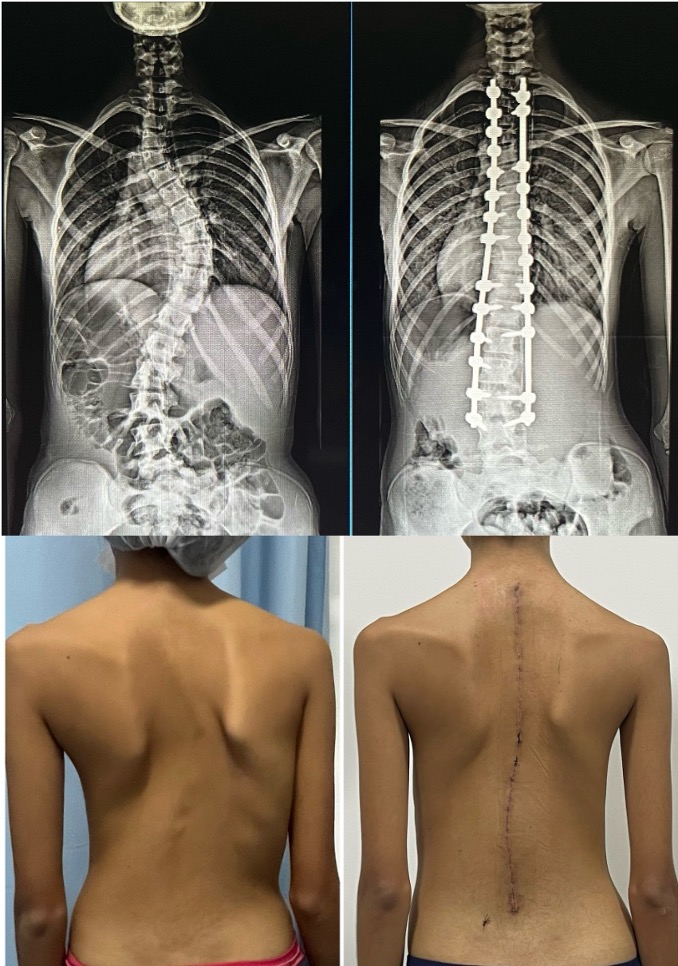

O tratamento cirúrgico tem como objetivo corrigir a deformidade, estabilizar a coluna e evitar progressão futura da curva.

Para isso, a cirurgia consiste na colocação de parafusos e hastes metálicas para alinhar a coluna. Após a correção, o cirurgião promove a artrodese, isto é, a união definitiva de determinadas vértebras. Esse processo envolve a preparação das superfícies ósseas para que os ossos se consolidem entre si, formando uma estrutura estável que mantém a correção obtida ao longo do tempo.

Partindo-se desse pressuposto, o objetivo da cirurgia é corrigir a deformidade, restaurar o alinhamento da coluna e evitar progressão futura, por meio de artrodese instrumentada com parafusos e hastes. Esses materiais geralmente são feitos de titânio ou cromo-cobalto e não têm necessidade de serem retirados posteriormente.

Ressecção de vértebra malformada (hemivértebra)

Quando a deformidade está concentrada em uma vértebra específica malformada, pode ser indicada a retirada cirúrgica dessa vértebra (hemivértebra), seguida de uma correção localizada com fusão curta.

Essa abordagem busca tratar a causa da deformidade, permitindo boa correção da curva e preservando o máximo possível da mobilidade da coluna nos segmentos não acometidos.